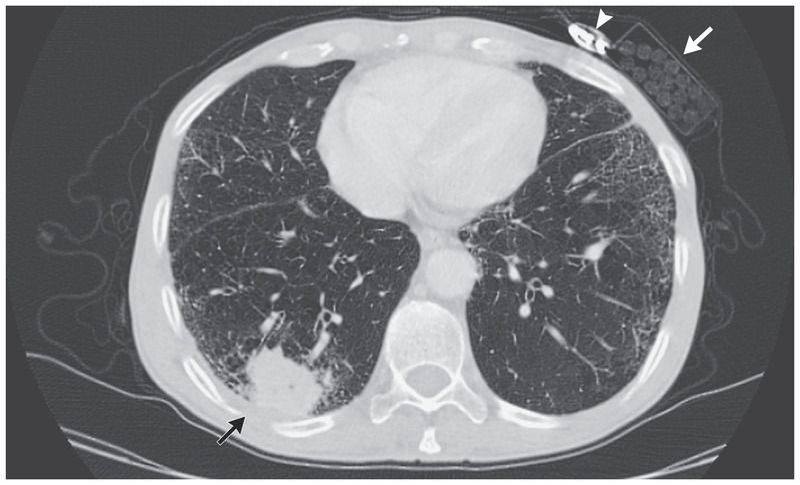

A 63-year-old man presented to the primary care clinic with a dry cough and a history of unintentional weight loss of 10 kg over the preceding 2 months. He was an active smoker, with a 30-pack-year history of tobacco smoking. Physical examination revealed decreased air entry in the base of the right lung. A chest radiograph showed opacity in the right lower lobe of the lung, and computed tomography of the chest performed after the administration of contrast material revealed a mass in the right lower lobe measuring 5.6 cm in its largest diameter (black arrow). Right hilar, carinal, and paratracheal lymphadenopathy was also present (not shown), and destruction of the posterior portion of the right seventh and eighth ribs was observed. A pack of cigarettes (white arrow) and a lighter (arrowhead) that were in his breast pocket were noted on the scan. Findings on bronchoscopy and biopsy confirmed a diagnosis of squamous-cell carcinoma, and staging evaluation indicated stage IV disease. Cigarette smoking is the leading risk factor for lung cancer. The patient was treated with palliative chemotherapy and radiation. He died 1 year after diagnosis.